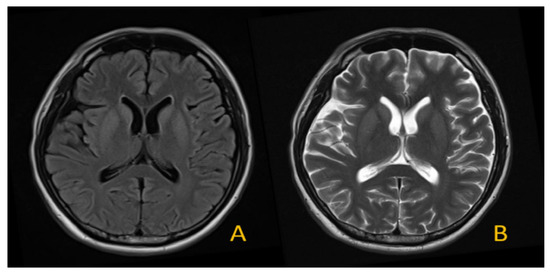

4.3. Dataset

4.4. Image Processing and Classification